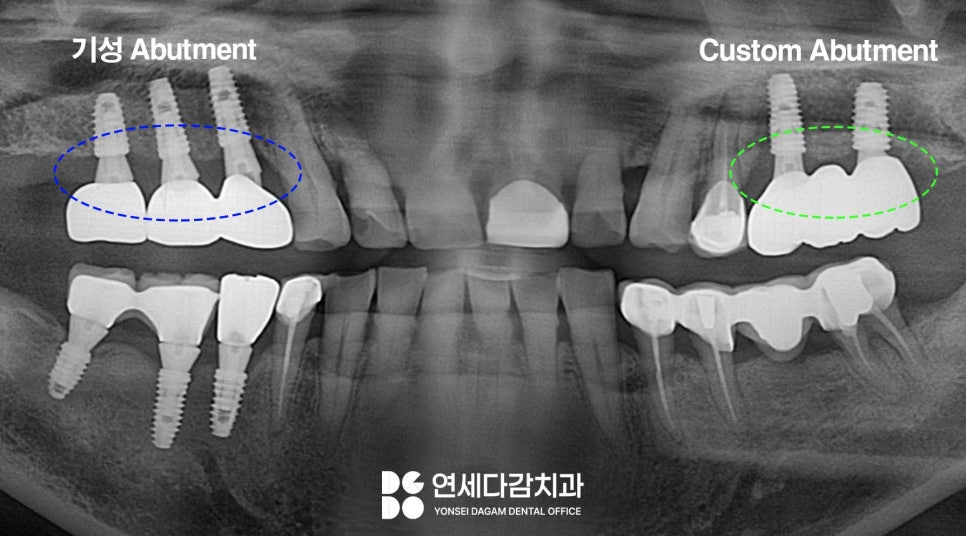

엑스레이를 살펴보면,

임플란트와 크라운이 연결된

부품의 형태가 다른 것을 볼 수 있습니다.

이 부위를 지대주 (=어버트먼트, abutment) 라고 하는데,

임플란트는 크게 세 부분으로 구성됩니다.

뼈 속에 심는 Fixture,

그 위에 연결되는 abutment,

그리고 눈에 보이는 crown입니다.

어버트먼트는 픽스처와 크라운을 연결하는

중간 기둥 역할을 하는데,

이 부품 종류로는

기성품과 맞춤 제작품이 있습니다.

기성 어버트먼트는 공장에서

미리 만들어진 규격화된 제품입니다.

비용이 상대적으로 낮다는 장점이 있으나,

개인의 잇몸 형태나 치아 각도에

적합도가 100% 맞지 않을 수 있습니다.

반면 커스텀 어버트먼트는 환자의 구강

형태에 맞게 개별 맞춤 제작하는 방식입니다.

잇몸 라인과 치아 형태에 맞게 설계되어

보철물과의 적합도가 높아집니다.